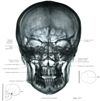

全体としての頭蓋